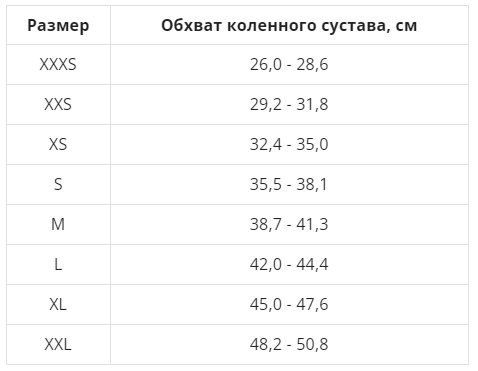

Циркулярный бандаж из неопрена со стабилизирующим силиконовым кольцом и отверстием над коленной чашечкой.

Характеристики